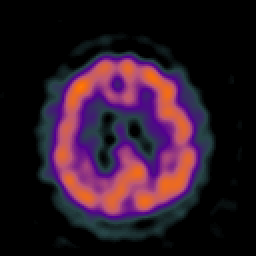

Huntington's Chorea, MR -- Slice #14

[Home][Help][Clinical] Slice 14